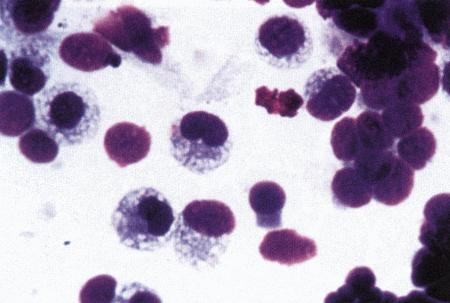

Фиг. 2.2.

Вагинальные выделения кошки (а). Выделения, типичные для фазы эструса. Большая часть клеток представляет собой безъядерные кератинизированные клетки или клетки с пикнотическим ядром. Присутствуют промежуточные клетки (b). Выделения, характерные для метэструса, — «течки», иногда наблюдаемой у кошек в конце эструса. Присутствуют поверхностные и промежуточные клетки, повышено содержание лейкоцитов. Этот короткий метэструс наблюдается в течение 24–48 часов (см. Приложение)